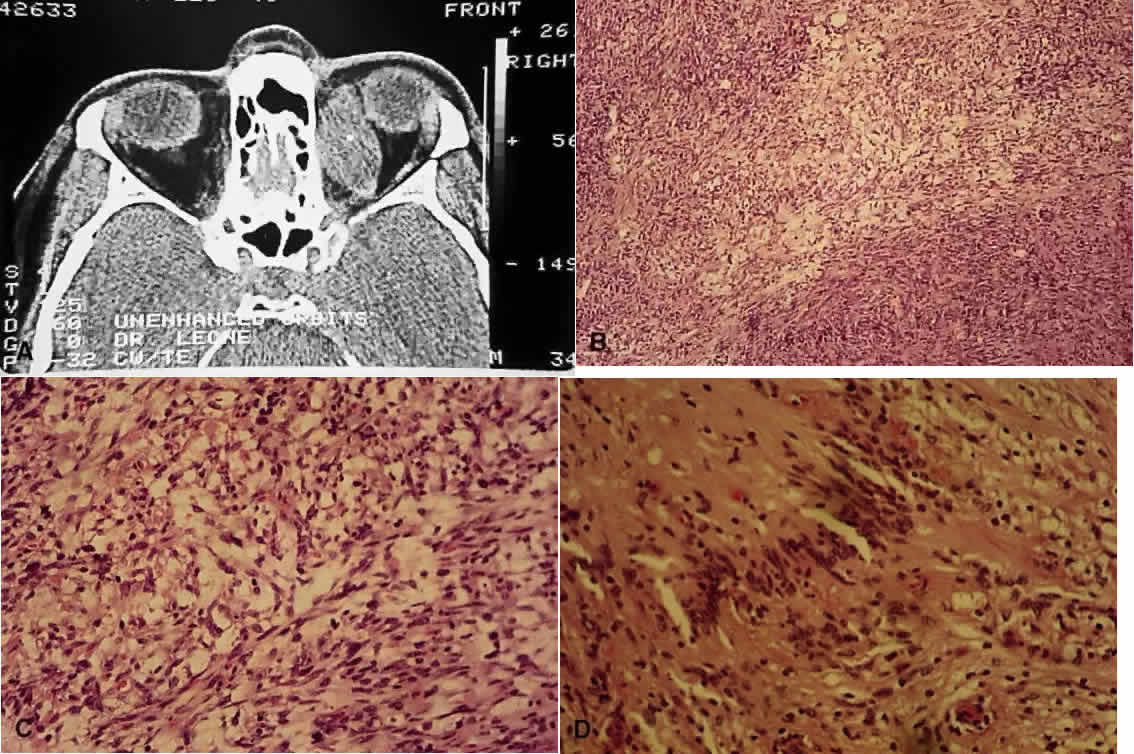

Schwannomas, or neurilemmomas, are proliferations of the Schwann cells that normally surround peripheral nerves. Histologically, two patterns can be evident—Antoni A, consisting of densely packed, swirling cells with indistinct cytoplasmic membranes, and Antoni B, which have a more mucoid appearance (Fig. 9). The eighth nerve tumors tend to cause deafness, so management of the cataracts becomes important to help preserve function. However, visual loss can also be caused by optic nerve and intracranial meningiomas.49 Retinal hamartomas occur in up to 22% of patients with NF2.39 In contrast, the occurrence of Lisch nodules and café-au-lait spots is unusual and not helpful in diagnosing NF2.48

Fig. 9. Neurilemmoma (schwannoma). A. Computed tomography scan of orbital neurilemmoma. B. Low-power view showing Antoni A (more densely packed cells) and Antoni B (more mucoid, paler areas) patterns (H&E, × 10). C. Higher-power view showing Antoni B pattern (H&E, × 25). D. High-power view of a Verocay body, where the long axes of the cell nuclei line up in register (H&E, × 31).